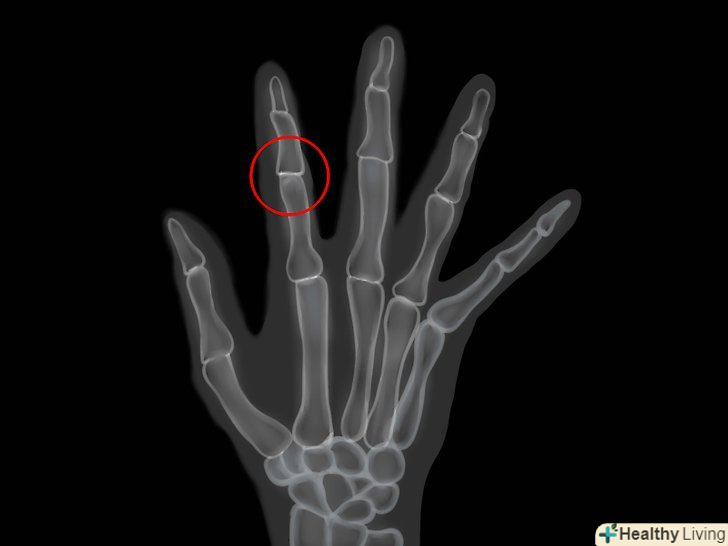

• Призначить обстеження, включаючи рентген та інші дослідження суглобів.